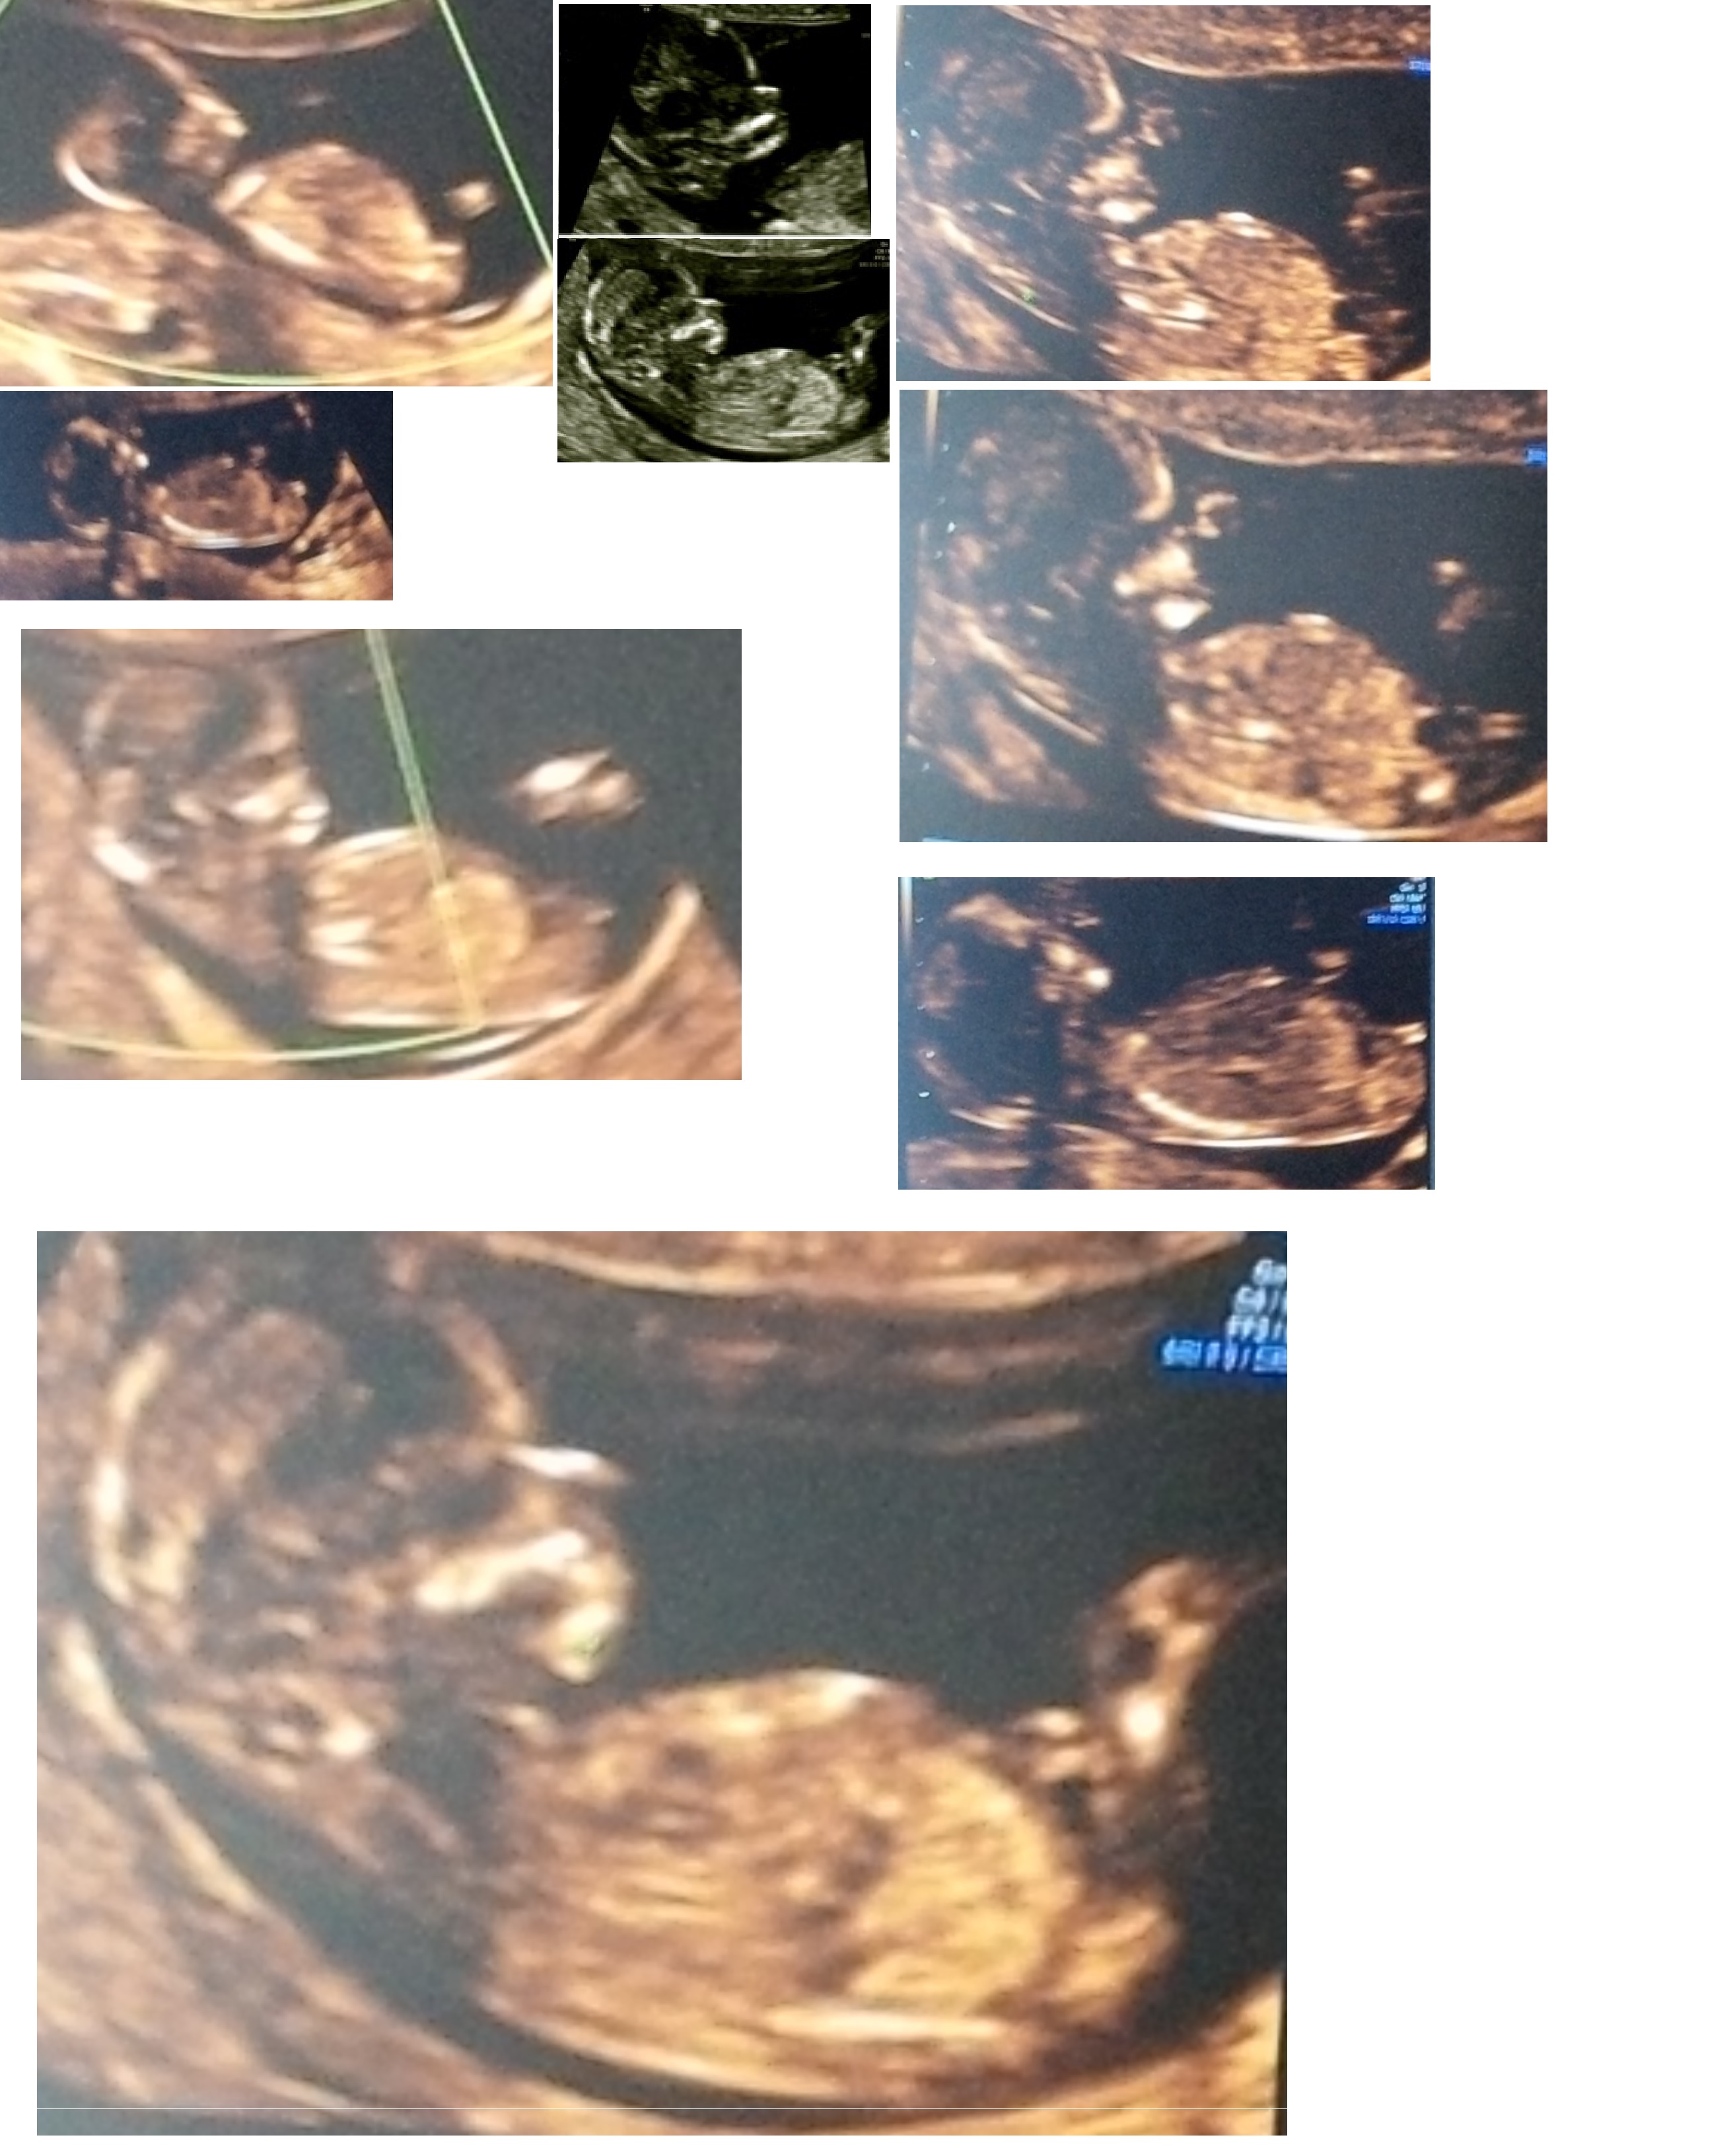

Hey everybody - we're struggling to figure this little one out...

Anybody care for an informed/seasoned prediction?

You will probably need to view the Full-sized version...

P.S. The images may seem a little blurry...it may be due to us getting a trainee sonographer...